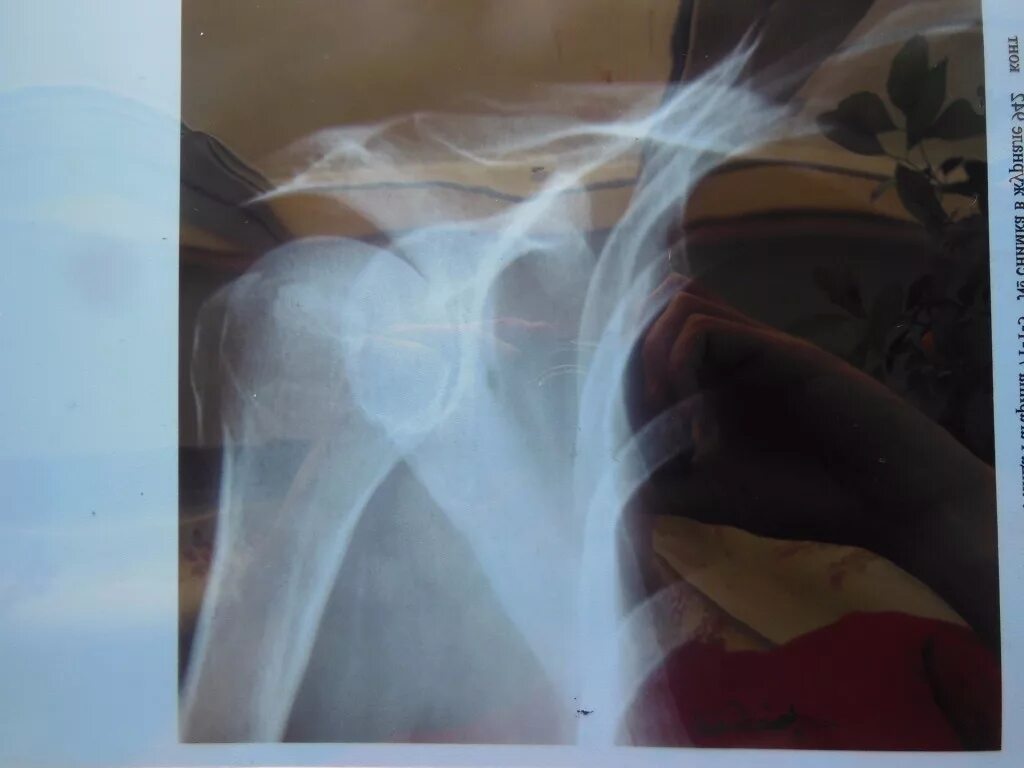

Перелом б бугорка